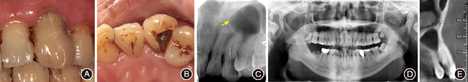

患者男性,35岁。左上尖牙钝痛2个月, 1天前于外院行牙髓治疗发现根尖区有一"大囊肿" ,遂就诊于中国医科大学口腔医学院牙体牙髓科。

一般检查可见

牙冠颜色较暗,远中腭侧龋坏且髓腔已开放,根管内探痛(+),叩痛(±),根尖区扪痛(-),无松动,颊腭侧牙龈无膨隆,未探及牙周袋。全口牙面大量烟斑及色素沉着,下前牙牙石(+~+++)(图1A、图1B)。牙髓活力电测试:

(15)。根尖X线片示

远中龋坏达髓腔,根尖可见倒锥形低密度透射区(1.5 cm×1.5 cm),边界清晰(图1 C)。曲面体层X线片示

根尖透射影位于根尖远中,与远中上颌窦有一骨壁相隔(图1D)。锥形束CT示

根尖牙周膜连续,根尖区与上颌窦底之间仅有薄层骨壁相隔(图1E)。

术前唇侧照片;B:

术前舌侧可见远中舌侧龋坏,髓腔开放;C:X线片示

根尖区呈倒锥形低密度透射影(箭头);D:曲面体层X线片示

根尖区低密度透射影与远中上颌窦有一薄层骨壁相隔;E:锥形束CT可见

根尖与上颌窦底紧密相连